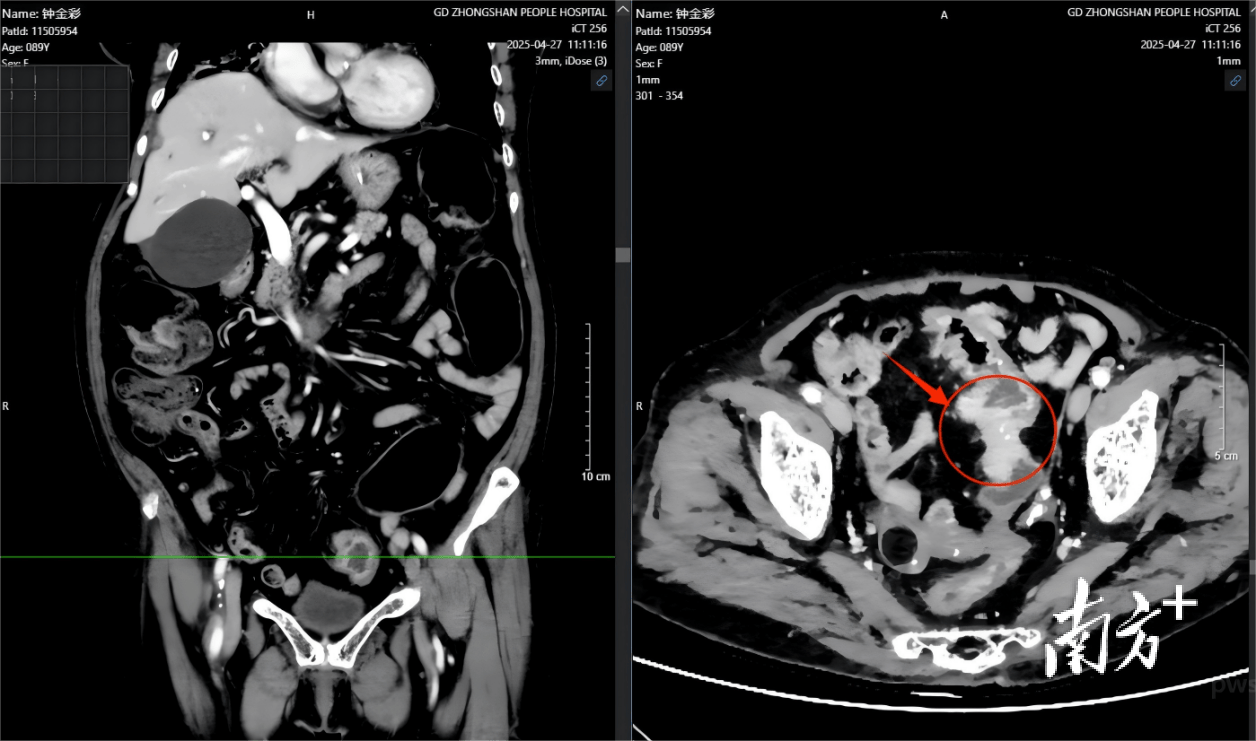

腹部增强CT示意图(红色箭头所指为乙状结肠占位)。 受访者 供图

4月下旬,钟阿婆因多日无法排气排便、并出现发热、气促,被紧急送至中山市人民医院,经快速、全面充分地评估,老人家不仅患有严重的肺炎、心功能不全、糖尿病等多种基础病,更是被发现有乙状结肠肿瘤并发肠梗阻。面对病情如此危重且复杂、手术风险极高的“90后”患者,是冒险手术,还是保守治疗?这不仅仅是一个医疗决策,更是一场关乎生命的抉择。